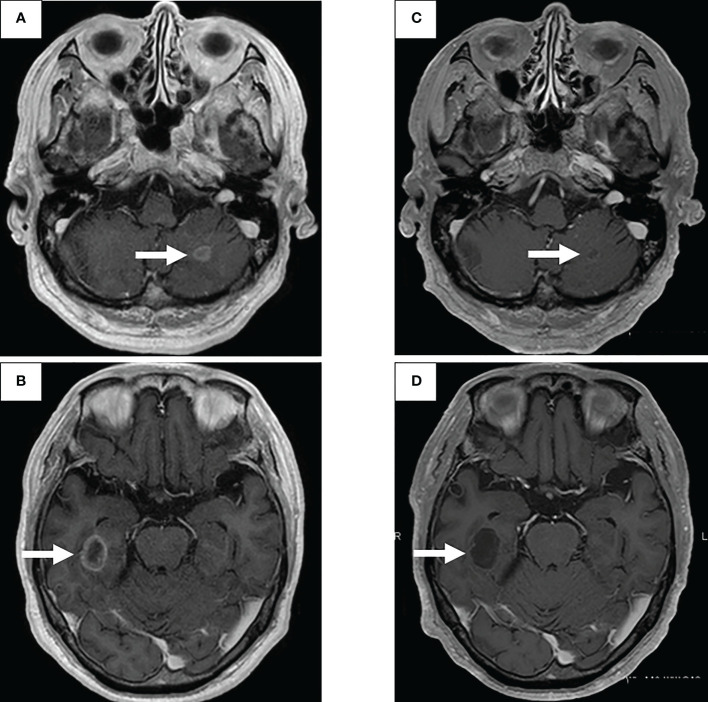

圖1:在先進次就診到開始進行第二次治療期間,患者7年間原發(fā)病灶的順序圖像

一線治療包括卡鉑+培美曲塞+貝伐單抗,經(jīng)過4個療程后獲得近乎有效緩解(CR),但鼻出血仍然持續(xù),僅進行培美曲塞維持治療。在維持治療的25個療程中實現(xiàn)了CR(圖1C),但由于腎功能輕微惡化,治療暫時中斷。治療結(jié)束后一年,CT顯示原發(fā)病灶輕微進展(圖1D),但反復(fù)速度較慢。確認(rèn)CT反復(fù)一年后(圖1E),重新開始培美曲塞單藥治療,原發(fā)病灶和淋巴結(jié)減?。▓D1F)。然而,在進行了32個維持治療療程后,出現(xiàn)了快速的全身進展。由于原發(fā)病灶再生(圖1G)、對側(cè)肺轉(zhuǎn)移、多發(fā)性肝轉(zhuǎn)移、右側(cè)腎上腺轉(zhuǎn)移和多發(fā)性腦轉(zhuǎn)移(圖2A、B),需要調(diào)整他的治療方案。

圖2:使用二線治療塞爾帕替尼的腦轉(zhuǎn)移療效

通過支氣管鏡對原發(fā)病灶進行再活檢,細胞學(xué)評估顯示V級腺癌,組織學(xué)評估證實了這一結(jié)果。腫瘤正確用藥850基因檢測確認(rèn)患者為RET融合基因陽性,隨后于第二天給予240mg塞爾帕替尼。第13天的CT顯示與基線影像相比(圖1H),所有轉(zhuǎn)移病灶,包括腦轉(zhuǎn)移(圖2C、D),均有良好的全身反應(yīng)。由于2級肝酶升高,繼續(xù)給予劑量減少的塞爾帕替尼(每天160mg)。使用高敏感度的下一代測序(NGS)面板系統(tǒng):肺癌緊湊面板,并使用細胞學(xué)刷液進行RNA檢測,證實了融合基因KIF5B外顯子15;RET外顯子12(K15RET12)。腫瘤正確藥基因解碼基因檢測還能夠從7年前的胸腔積液細胞塊的福爾馬林固定石蠟包埋(FFPE)標(biāo)本中進一步確認(rèn)RET(圖3A、B),這些標(biāo)本在惡性細胞的形態(tài)學(xué)上與再活檢樣本相似,具有大核仁(圖3C、D)。從初始細胞塊樣本中收集到的RNA(1256ng)具有RNA整合數(shù)(RIN)值為4.8。單重PCR和NGS檢測均檢測到了K15RET12融合峰(圖3)。